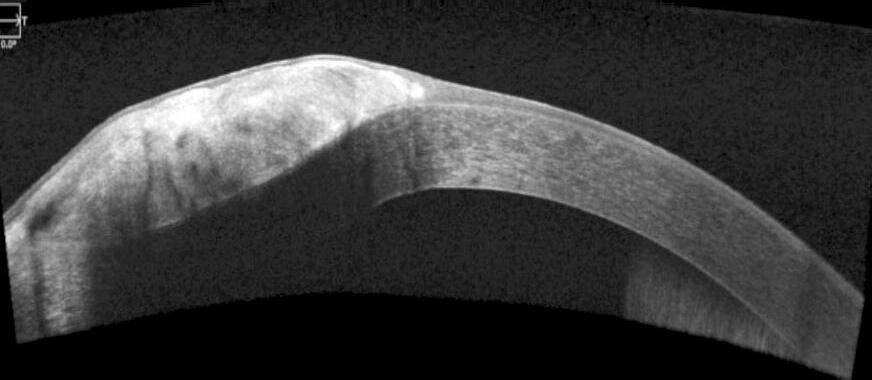

de las mismas hacia el limbo y el centro, FIG. 1. En la AOCT se observa la imagen de una formación que altera la superficie de la córnea, de carácter subepitelial que respeta la Membrana de Bowman . FIG. 2

FIG. 2: A-OCT PREOPERATORIA.